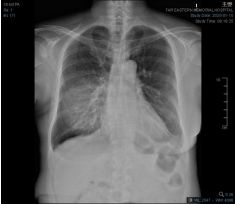

7.CC: cough for one year and back pain